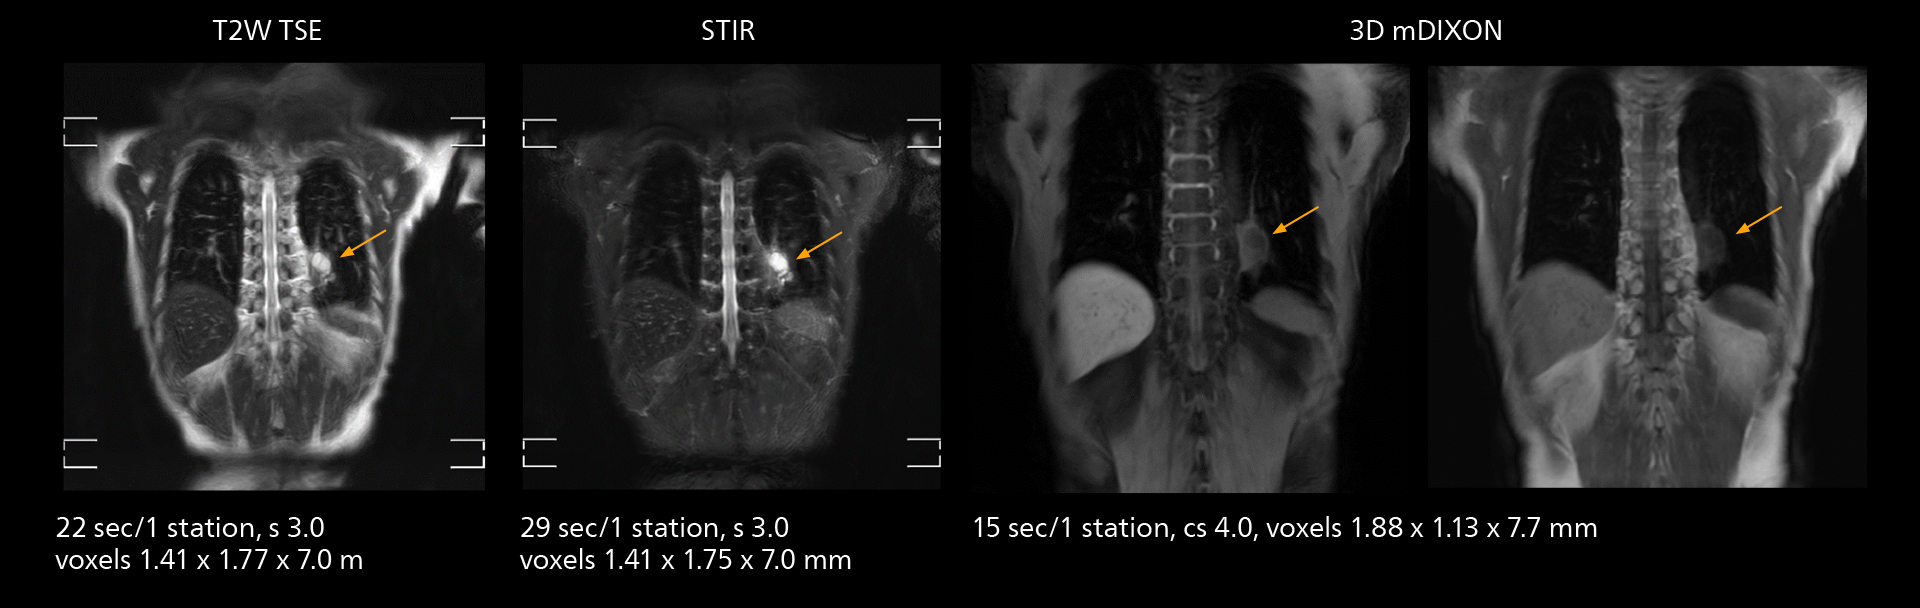

The value of the Elition X gradients is also evident in DWIBS studies. “The fact that we can consistently obtain distortion‐free DWIBS while reducing imaging time at three coronal stations is excellent,” Dr. Makuuchi says. “In these patients, it’s also important that the application of Compressed SENSE to T2‐weighted, STIR and mDIXON sequences has no impact on the examination time of whole‐body imaging. As a result of the increased speed and higher image quality we realize, DWIBS studies have now become routine examinations.”

Fast whole body DWIBS examination

With SmartPath to Elition X the team can obtain excellent quality DWIBS imaging and reduce imaging time. Other sequences also fit in the examination slot. This case shows left paravertebral neurogenic tumor and Th10 vertebral hemangiomas.

Fast whole body DWIBS examination

With SmartPath to Elition X the team can obtain excellent quality DWIBS imaging and reduce imaging time. Other sequences also fit in the examination slot. This case shows left paravertebral neurogenic tumor and Th10 vertebral hemangiomas.